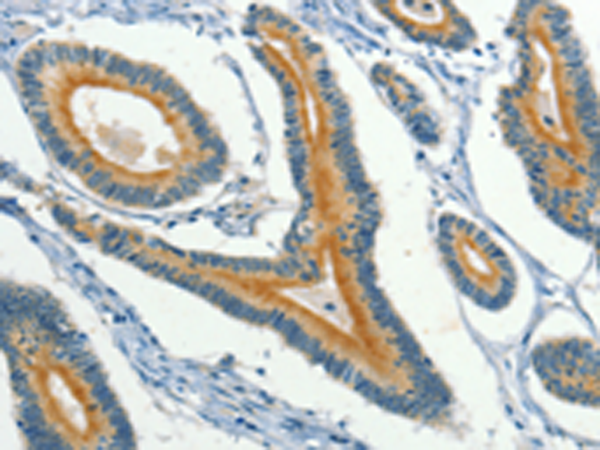

分类: 科研抗体货号: P08005别名: NT; eN; NT5; NTE; eNT; CD73; E5NT; CALJA应用: IHC反应种属: Human, Mouse, Rat